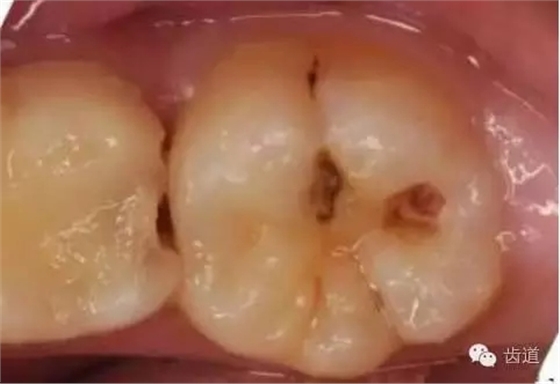

1、淺齲:指釉質(zhì)齲,發(fā)生于牙頸部時為牙骨質(zhì)齲和(或)牙本質(zhì)齲。

2、中齲:牙本質(zhì)淺層齲。

3、深齲:牙本質(zhì)深層齲

4、可疑齲:指窩溝處較深,色黑,有患齲傾向,未形成典型淺齲。